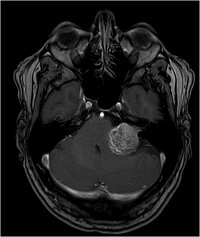

Akustikusneurinom T1 - axial

Akustikusneurinom T2 - axial